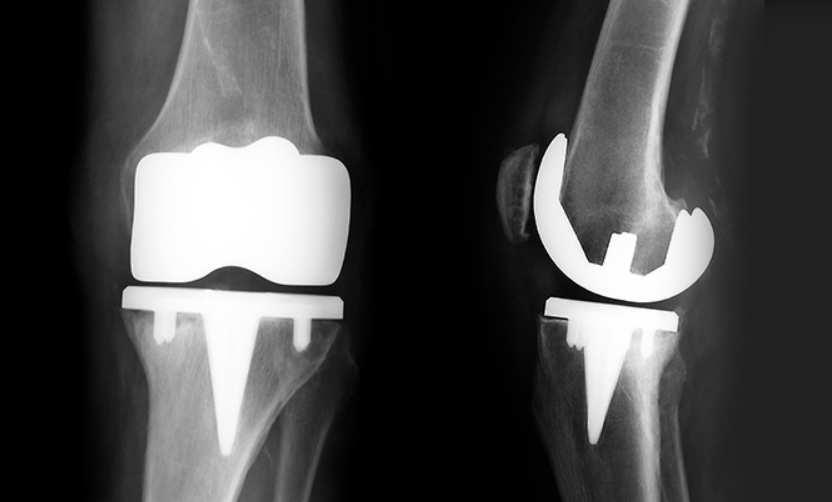

무릎 인공관절 수술은 손상된 관절을 금속이나 특수 플라스틱 재질의 인공관절로 바꾸는 수술이에요. 대표적으로 퇴행성 관절염이 심해져 약물이나 물리치료로는 더 이상 효과를 보기 어려운 경우에 시행돼요.

무릎 인공관절 수술을 받게 되면 가장 큰 장점은 통증에서 해방된다는 거예요. 걷기, 계단 오르내리기, 가벼운 운동까지 가능해지고, 휘어진 다리가 곧게 펴지는 효과도 있어요.

많은 환자들이 수술 전 무릎이 잘 펴지지 않거나 70도 이상 구부리기 힘들어하는 경우가 있는데요, 수술 후에는 대부분 100도 이상 구부릴 수 있고, 심한 경우가 아니면 생활에 큰 제약 없이 움직일 수 있게 돼요.

단, 인공관절은 정상 관절이 아니라는 점은 잊지 마셔야 해요. 격렬한 운동, 농사일, 쪼그려 앉는 동작은 인공관절 수명을 줄이기 때문에 피하셔야 해요.